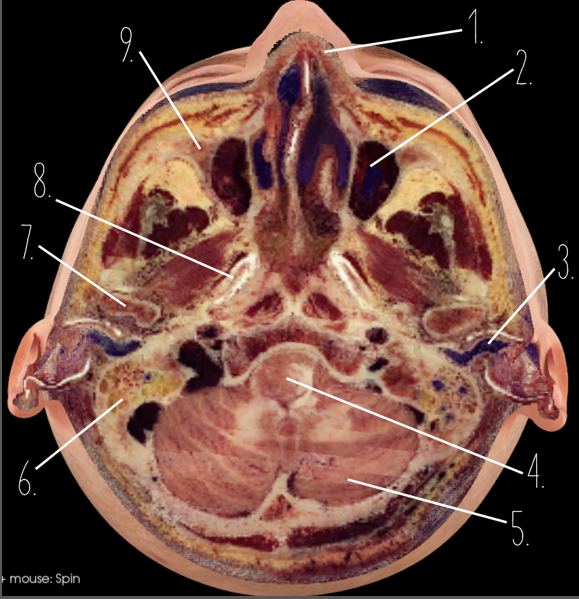

1?

Nasal Bone

2?

Maxillary Sinus

3?

External Acoustic Meatus

4?

Pons

5?

Cerebellum

6?

Mastoid Air Cells

7?

Mandibular Condyles

8?

Sphenoid Bone

9?

Maxillary Bone